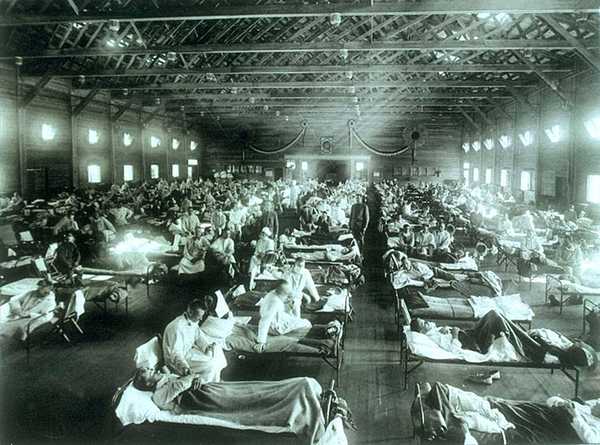

1918年

西班牙流感大流行,导致2100万至5000万人死亡,这是历史上死亡人数最多的一次,并且死亡人口多数是年轻人。这可能因为第一次世界大战期间的士兵的密切接触而传播,并导致了全球的大流行。